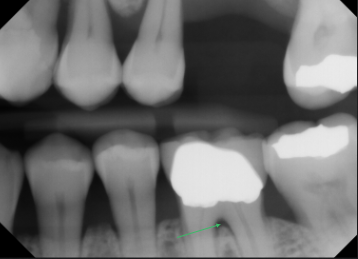

first radiographic sign of furcation involvement

pdl widening at furcation

bone loss with furcation involvment

osseous defects in furcation of multirooted teeth